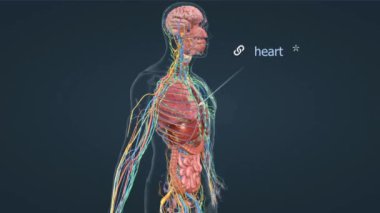

damarlarkalpnabızAtardamarlarkılcalKan basıncıdamar sistemikan damarlarıKan dolaşımıkan akımıDolaşım Sistemikan desteğikardiyovasküler sistematık kaldırmaoksijen taşımaLenfatik SistemPulmoner dolaşımSistemik dolaşımkalp ve damar sağlığıdamar dokusudeoxygenated bloodheart functionendotel hücreleriBesin taşımacılığıoxygenated bloodvascular smooth musclekan dağılımıgemi duvarlarıvasküler sağlıkarterial functionDolaşım sisteminin sağlığıvessel lumenblood vessel functionKan akışı düzenlemesiKan damarları anatomisiKan damarı onarımıKılcal fonksiyonKan damarı esnekliğiKan damarı katmanlarıKan damarı yeniden yapılanıyorDoku perfüzyonuKan dolaşımı yollarıKılcal değişimDolaşım yoluKan damarı çapıvenöz fonksiyonBenzer İçerikler